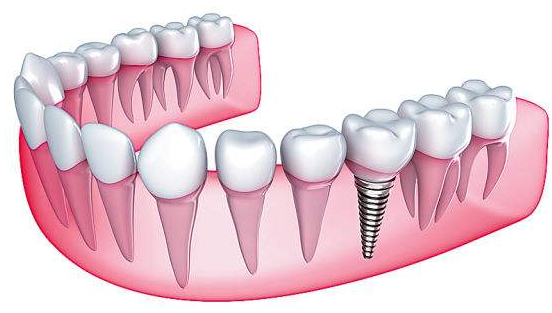

种牙是将人工牙根植入缺牙部位的牙床内,当牙根与牙床长牢后,再在牙根上接一颗逼真的瓷牙,这样,种好的人工牙既牢固又美观,而且结实耐用为人类的第三副牙齿。

种植牙时不会对邻牙正常组织造成影响,更不会有异物感或不舒服感等不适感觉。而传统镶牙,则需要将缺牙两边邻近牙齿磨小,以作为固定牙套的支撑,除此之外,在口腔内也会使人们感觉不舒服。

2、牙齿修复后的固位程度不同

传统镶牙与种植牙对牙齿修复,都可能造成牙龈损害、牙槽骨萎缩等现象。但在牙齿缺失比较厉害的情况下,传统镶牙会以依靠牙床粘膜软组织为支撑,因此容易发生固位不好,牙齿活动的现象。而种牙虽相对比较适应牙齿缺失较少的情况,但是固位效果较好,一般不会出现牙齿移动现象。

3、对正常咀嚼功能的影响不同

传统镶牙修复牙齿缺漏后,可能会损坏其它牙齿,导致口腔内牙齿整体的咀嚼能力变差变弱。且镶牙后,容易积淀脏物,不易清理,影响牙齿美观。而种植牙修复牙齿,密合性非常好,不会出现传统镶牙的上述弊端。